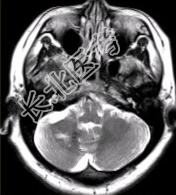

- [材料题] 患者女,41岁。头痛半年,加重10d。头部MRI显示如下图。

- 简答题1、请对该病的MRI进行描述。